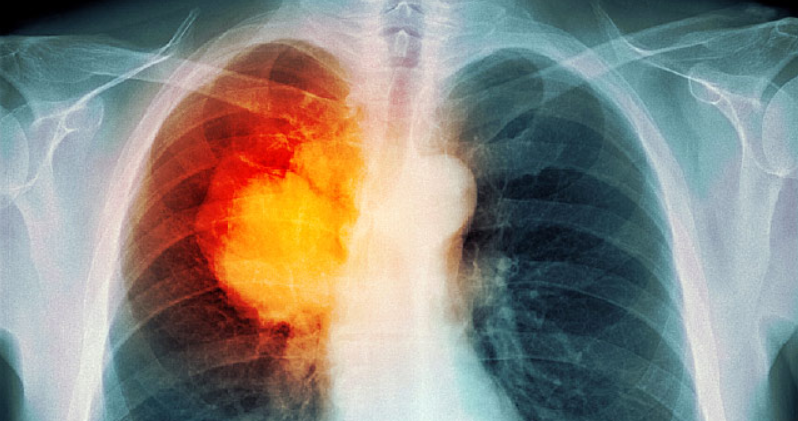

폐암으로 인한 허리 통증은 이러한 많은 질환과 공통점을 공유하지만 그것의 뚜렷한 차이점이 있습니다. 이 중 상당 부분은 암이 직접적으로나 간접적으로 통증을 유발하는 방법과 장소와 관련이 있습니다. 폐암이 허리 통증을 유발할 수 있는 몇 가지 가능한 방법은 다음과 같습니다.

종양이 직접적으로 가해지는 압력은 허리 구조보다 중반에서 상층부에 위치할 수 있습니다. 악성 종양이 폐와 가슴 벽의 안감을 치료하는 신경을 자극하여 나라 돕고 때로는 만성 신경통을 유발할 수 있는 방법.

폐에서 척추 및 뼈로의 악성 종양의 전이 (전이)는 폐암 환자의 30 % 이상이 공유하는 현상입니다. 부신에 암이 전이된 경우 (폐암 환자의 40 % 에서 발생) 신장 바로 위의 위치 때문에 국부적인 통증을 유발합니다.